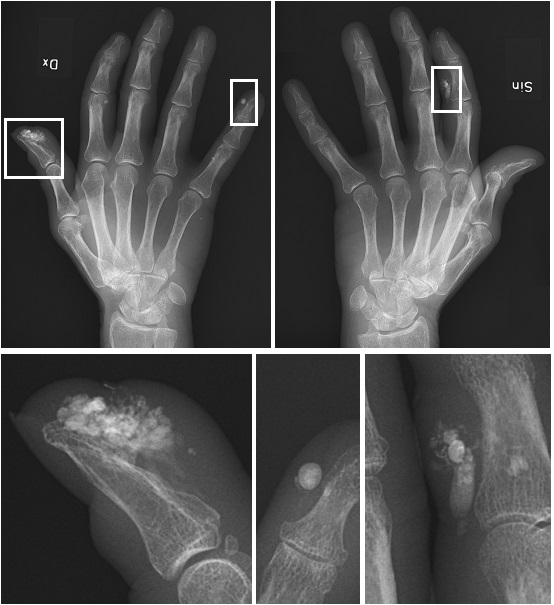

CREST 증후군 (석회증과 손발가락경화증)

CREST 증후군(석회증 및 경화지증)

CREST 증후군에서 미세 석회화를 보여주는 X-레이

• Calcinosis(석회증): 피부가 두꺼워지고 팽팽해지며 칼슘 침착 결절이 생긴다.

2. 1. 석회증 (Calcinosis)

피부가 두꺼워지고 팽팽해지며 칼슘 침착 결절(Calcinosis|칼시노시스영어)이 생긴다.[1]